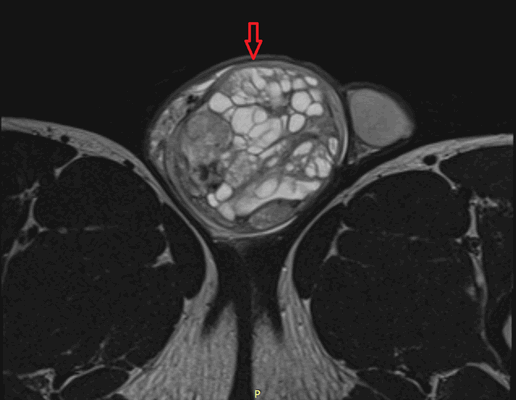

Рисунок 2. - семинома яичка: а — макропрепарат, б — МРТ.

По гистологической (то есть тканевой) структуре это наиболее часто новообразования желточного мешка либо доброкачественные тератомы.

Второй пик возникновения опухолей яичка - пубертат. В этот период растет частота заболеваемости злокачественными тератомами. Семиномы встречаются у детей крайне редко.